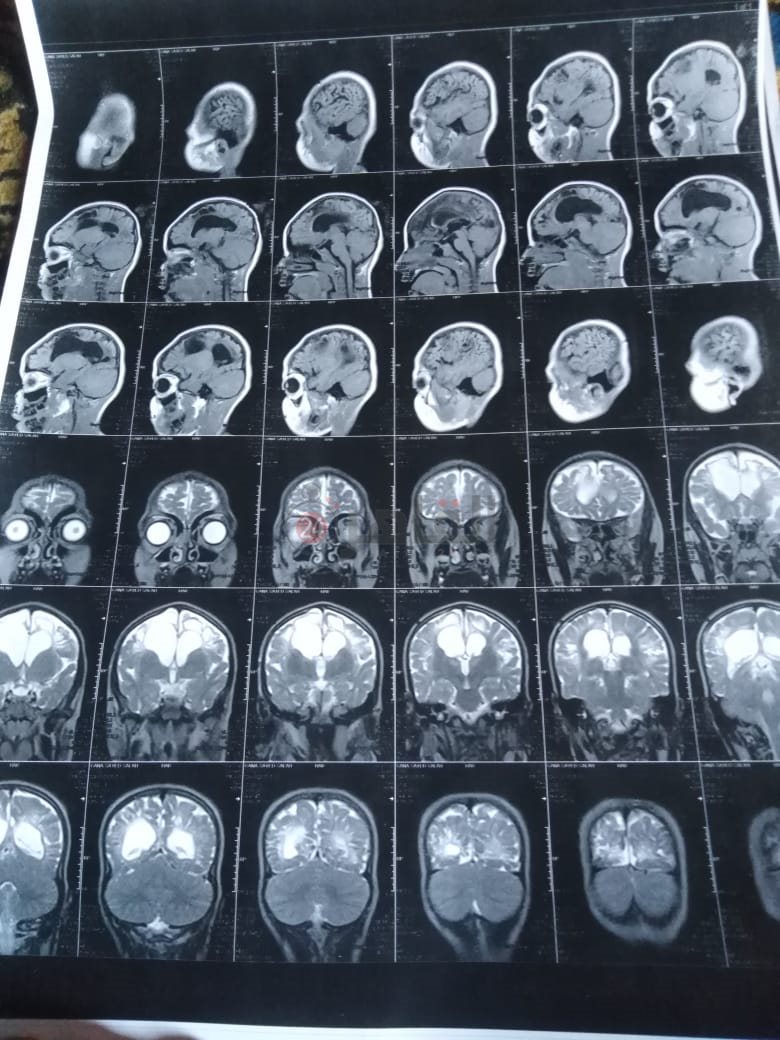

من جانبه، قال صلاح سيد، والد الطفلة جنى صلاح، إن ابنته تعاني من ضمور في المخ منذ ولادتها، نتيجة خطأ طبي، أدى إلى نقص كبير في الأكسجين لديها.

وأضاف في تصريحات خاصة لـ "القاهرة 24": "جنى تبلغ من العمر 6 سنوات، لا تستطيع المشي أو الوقوف على قدميها، نتيجة إصابتها بضمور في المخ منذ ولادتها".

وتابع: "مكنتش بتتحرك خالص، وجسمها طري، روحت كشفت عليها، وعملت أشعة وتحاليل كتير، أتأكدنا إصابتها بضمور في المخ"، مضيفًا:" مش بتعرف تأكل احنا اللي بنأكلها، هي عقلها كويس لكن مش بتتحرك ولا تتكلم".

وأوضح أن الطبيب الخاص بها أكد أن هناك داء خارج مصر يحسن من حالتها، ولكن باهظ الثمن، وتحتاج تناوله بشكل دوري.